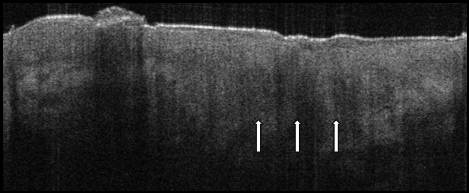

• Complete absence of the DEJ in the area of invasion

• Loss of mottled collagen texture and increased hyporeflectivity due to squamous cells